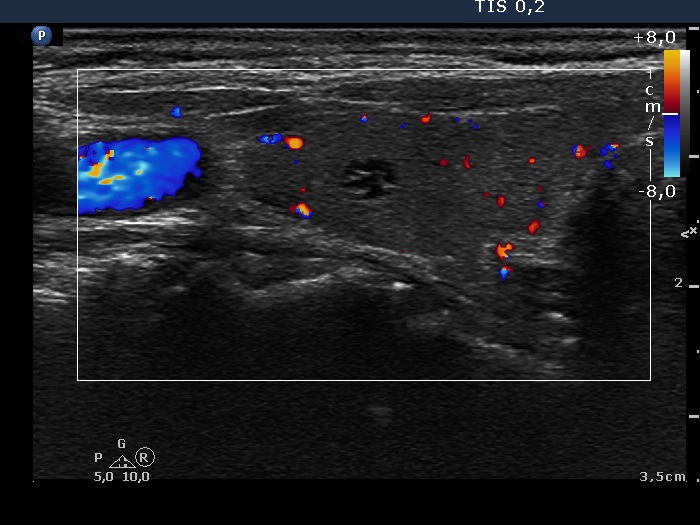

Clinical presentation: A 77-year-old woman was referred for evaluation of diffuse complaints suggesting hypothyroidism.

Ultrasonography. The thyroid was minimally hypoechogenic. There was a small cystic area in the central part of the right lobe. The maximal diameter of the lesion was 4 mm. It contained small hyperechogenic figures caused by posterior back wall enhancement.

Diagnosis: a healthy thyroid. Two of the cystic lesions were aspirated and cytology resulted in benign cystic-colloid lesion in both locations.